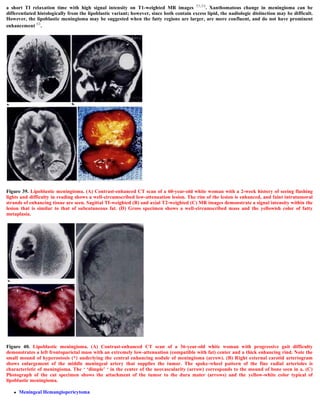

Figure 19. MRI T1 pre and postcontrast showing a convexity syncytial meningioma. The tumour is hypointense on the precontrast scan (A),

with an apparent CSF cleft, dense enhancement and a meningeal tail on the postcontrast scan.

Anther characteristic feature is the existence meningeal tail on the enhanced T1 images. The tail extends to a variable degree away from the

meningioma site. This tail does not represent neoplastic infiltration and may instead reflect fibrovascular proliferation in reaction to the

tumour.

Diagnosis of meningiomas using MR imaging is made by demonstrating the extra-axial nature of the mass. Several key MR imaging signs aid

in this distinction including: (1) the CSF cleft sign (a cleft of CSF between the lesion and the brain); (2) direct visualization of displaced or

involved dura; (3) demonstration of displaced pial vessels, which lie between the brain and the extra-axial mass; and (4) buckling of the gray-

white matter junction. 8,9 Meningiomas are thus characterized by the existence of a hypointense cleft between the tumour and the brain that

probably represents blood vessels or a CSF interface.

Figure 23. MRI T1 precontrast A,B and postcontrast

C,D,E, and MRI T2 image F, showing two syncytial

meningiomas in the same patient, notice the CSF cleft

A,F, the cystic changes (both intratumoural and

intraparenchymal) A,D, the intense postcontrast

enhancement, D,E,F, the meningeal tail D,E. Also notice

that the tumour is slightly hyperintense on the MRI T2

image F. There is also compression and displacement of

the 4th ventricle.

Figure 24. The psammomatous meningioma is

hypointense on the T2 images